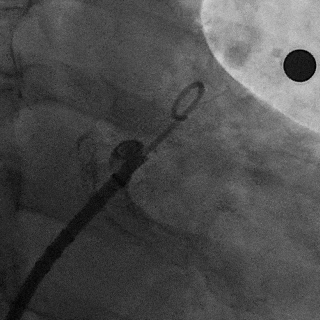

术中封堵器展开过程

鞘管定位

展开过程

Lefort封堵器展开后DSA评估和调整

肝位即刻造影,位置合适,上下缘无造影剂漏

牵拉时造影,有明显回弹,牵拉后位置无移动

封堵器未肩部

锚定区压缩比10%